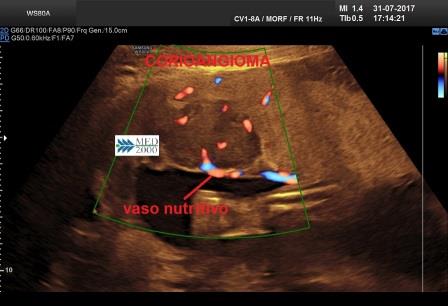

Altra caratteristica evidenziabile al Color-Doppler è un evidente flusso ematico e/o un grande vaso nutritivo afferente.

Le caratteristiche vascolari lo distinguono da altre neoformazioni placentari quali l'ematoma, la deposizione subcoriale di fibrina, la degenerazione idropica, un leiomioma in degenerazione adiacente alla placenta, un teratoma placentare.